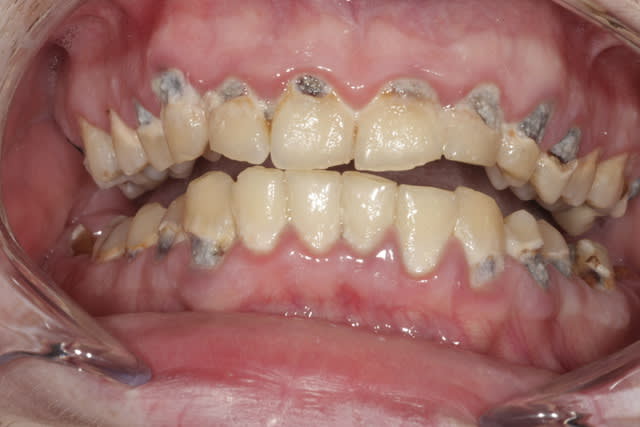

un cas qui me tient à coeur . j'ai pu sauvé toutes les dents après reprise des traitements canalaires et ma prothésiste a pas mal bossé

Agrys avant qpj067 - Eugenol

Photo 019 cr dy4tzg - Eugenol

Photo 446 cr cdjv8w - Eugenol

Photo 447 cr anuc1u - Eugenol

Photo 445 cr xbqinx - Eugenol